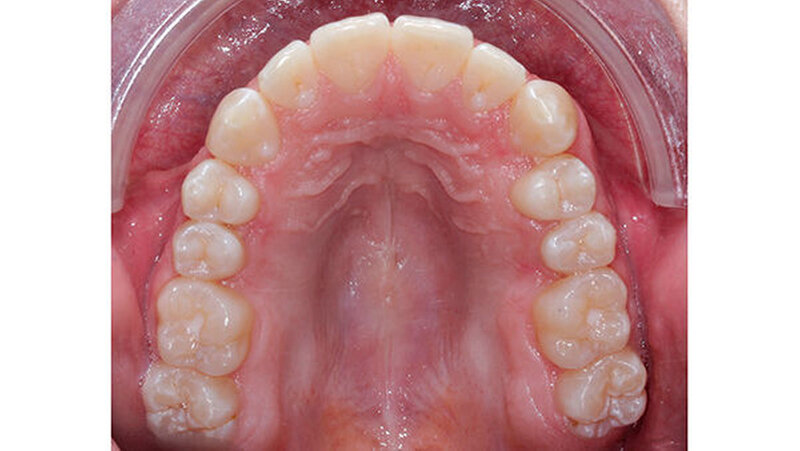

Dieser Fallbericht zeigt eine Patientin mit einer Transposition und multiplen verlagerten Zähnen, die mithilfe eines Gaumenimplantats eingeordnet wurden. Das Mädchen stellte sich im Alter von 13,7 Jahren in unserer Praxis vor. Bei der klinischen Untersuchung fiel die Persistenz mehrerer Milchzähne auf. Der Zahn 13 war distal des Milchzahns 53 durchgebrochen.

Im Rahmen der Modellanalyse ergaben sich folgende Befunde: Im Oberkiefer lagen außer der Transposition der Zähne 13 und 14 multiple Rotationen und Kippstände vor. Die Unterkieferfront wies einen Engstand auf. Im Molarenbereich lag beidseits eine Distalokklusion von ¼ Prämolarenbreite vor. Der Overjet betrug 2 mm, der Overbite 3 mm. Die Zähne 22/33, sowie 24/74 wiesen eine Kopfbissrelation auf.

Nach dreijähriger kieferorthopädischer Behandlung konnte die Patientin entbändert werden. Eine Stabilisierungsphase mit herausnehmbaren Essixschienen folgte. Nach Ende der aktiven Behandlungszeit waren die Therapieziele weitgehend erfolgreich umgesetzt worden.